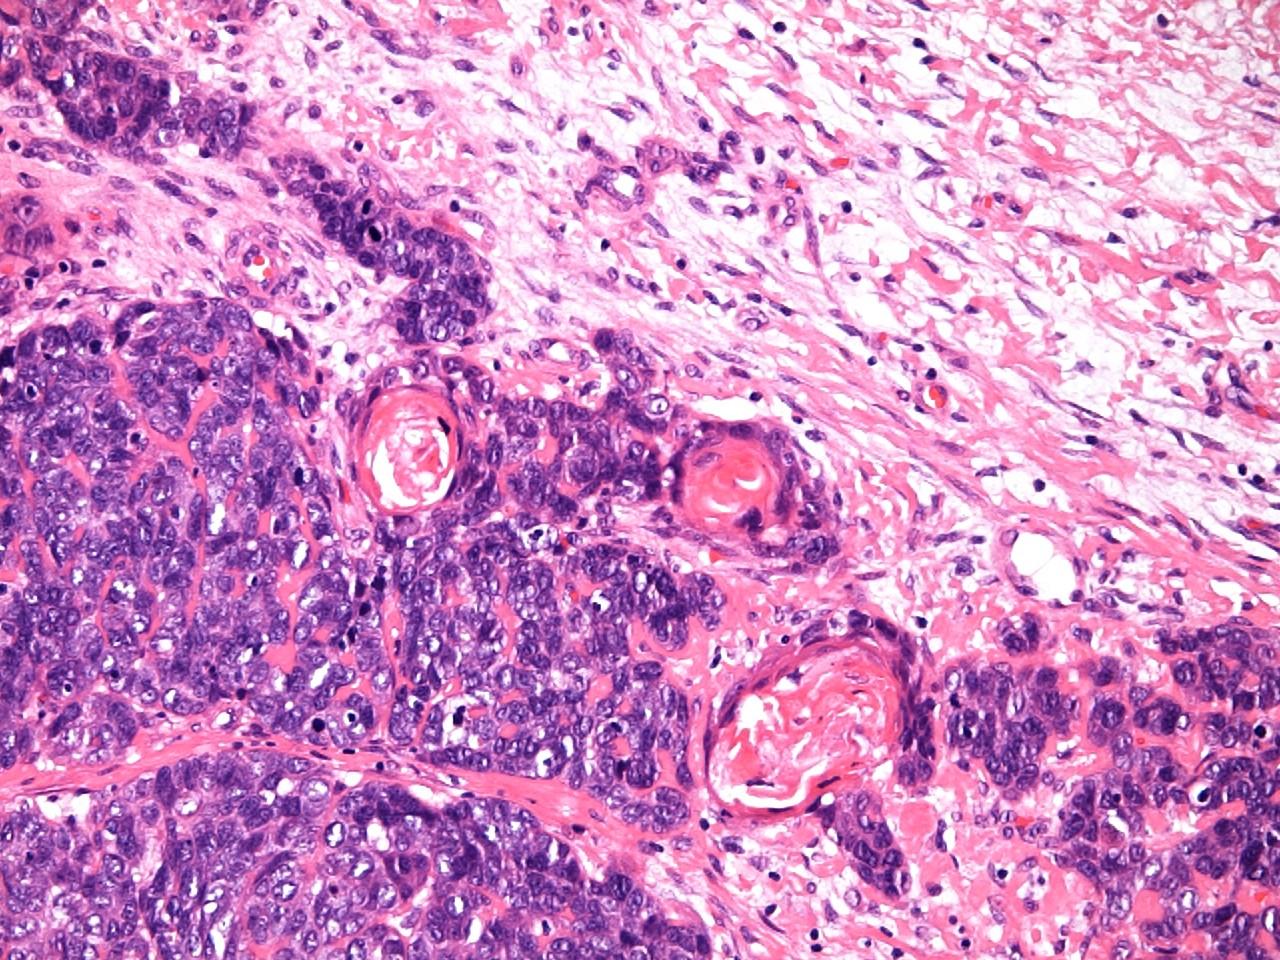

a, Proliferation of small to large, pleomorphic lymphoma cells

b, Lymphoma cells are invading a vein (arrows)

d, Expression of EBER1 in nuclei of lymphoma cells (EBER in situ hybridization,) Biopsy findings for the nasopharynx prior to radiotherapy.

c, Positive reactions for UCHL-1 are evident on the cytoplasmic membranes of lymphoma cells